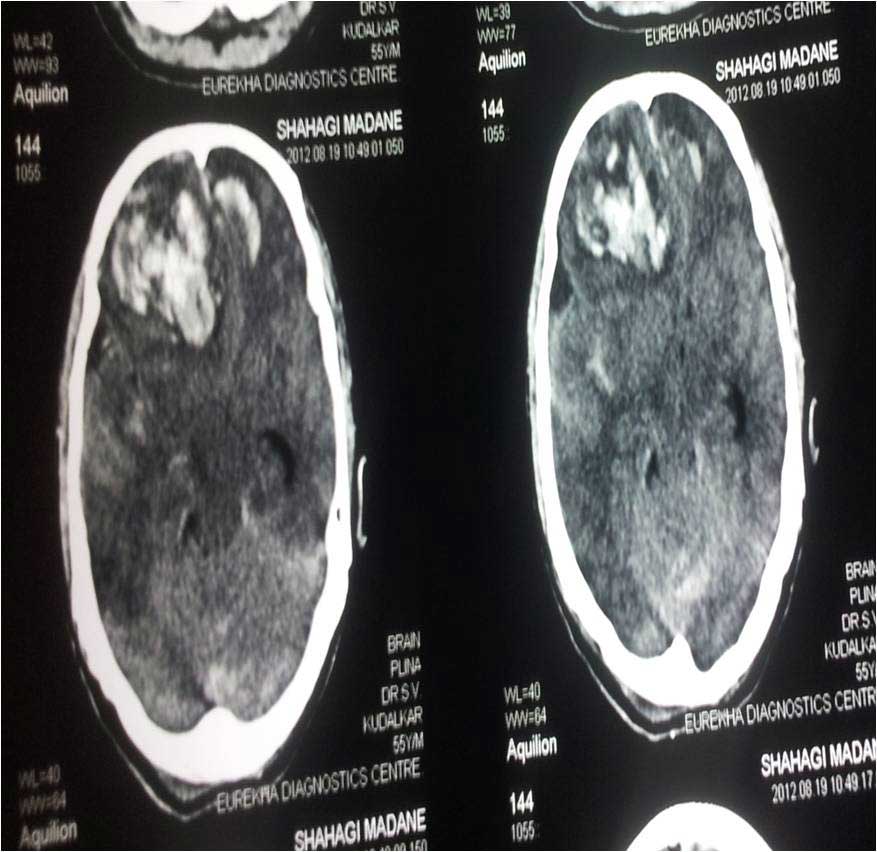

Brain Contusion Post OP CT of Bifrontal Contusion Brain X-Ray Bifrontal Contusion Pre OP intra op photo of contusion Brain Abscess Post OP 2 Clinical Brain Abscess Post OP 2 Clinical Brain Abscess Post OP 2 Clinical Brain Abscess Post OP 2 Clinical Brain Abscess Post OP 2 Clinical Brain Abscess Post OP 2 Clinical